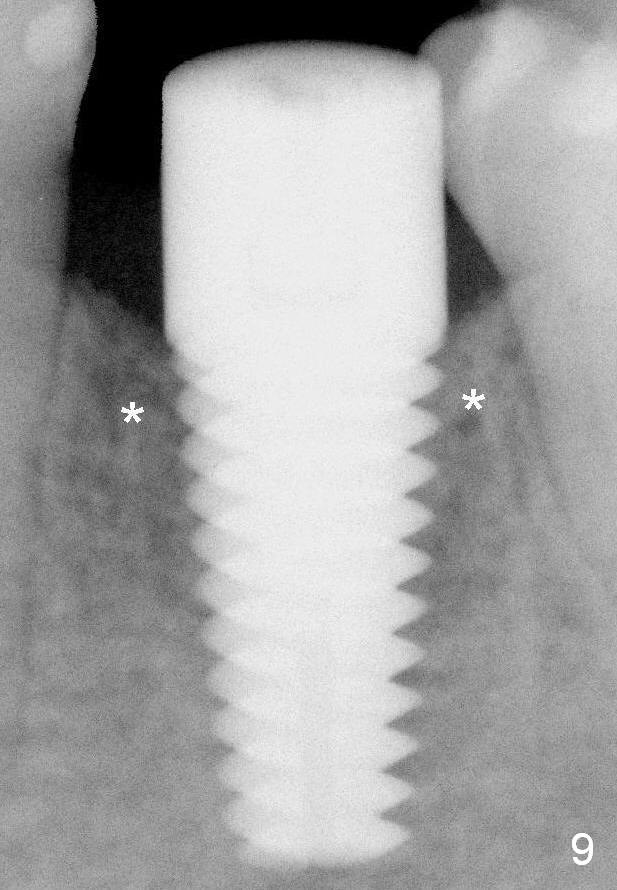

Fig.9 (6 months postop): Bone density around the coronal aspect of the implant increases (*). Apical resorption occurs.